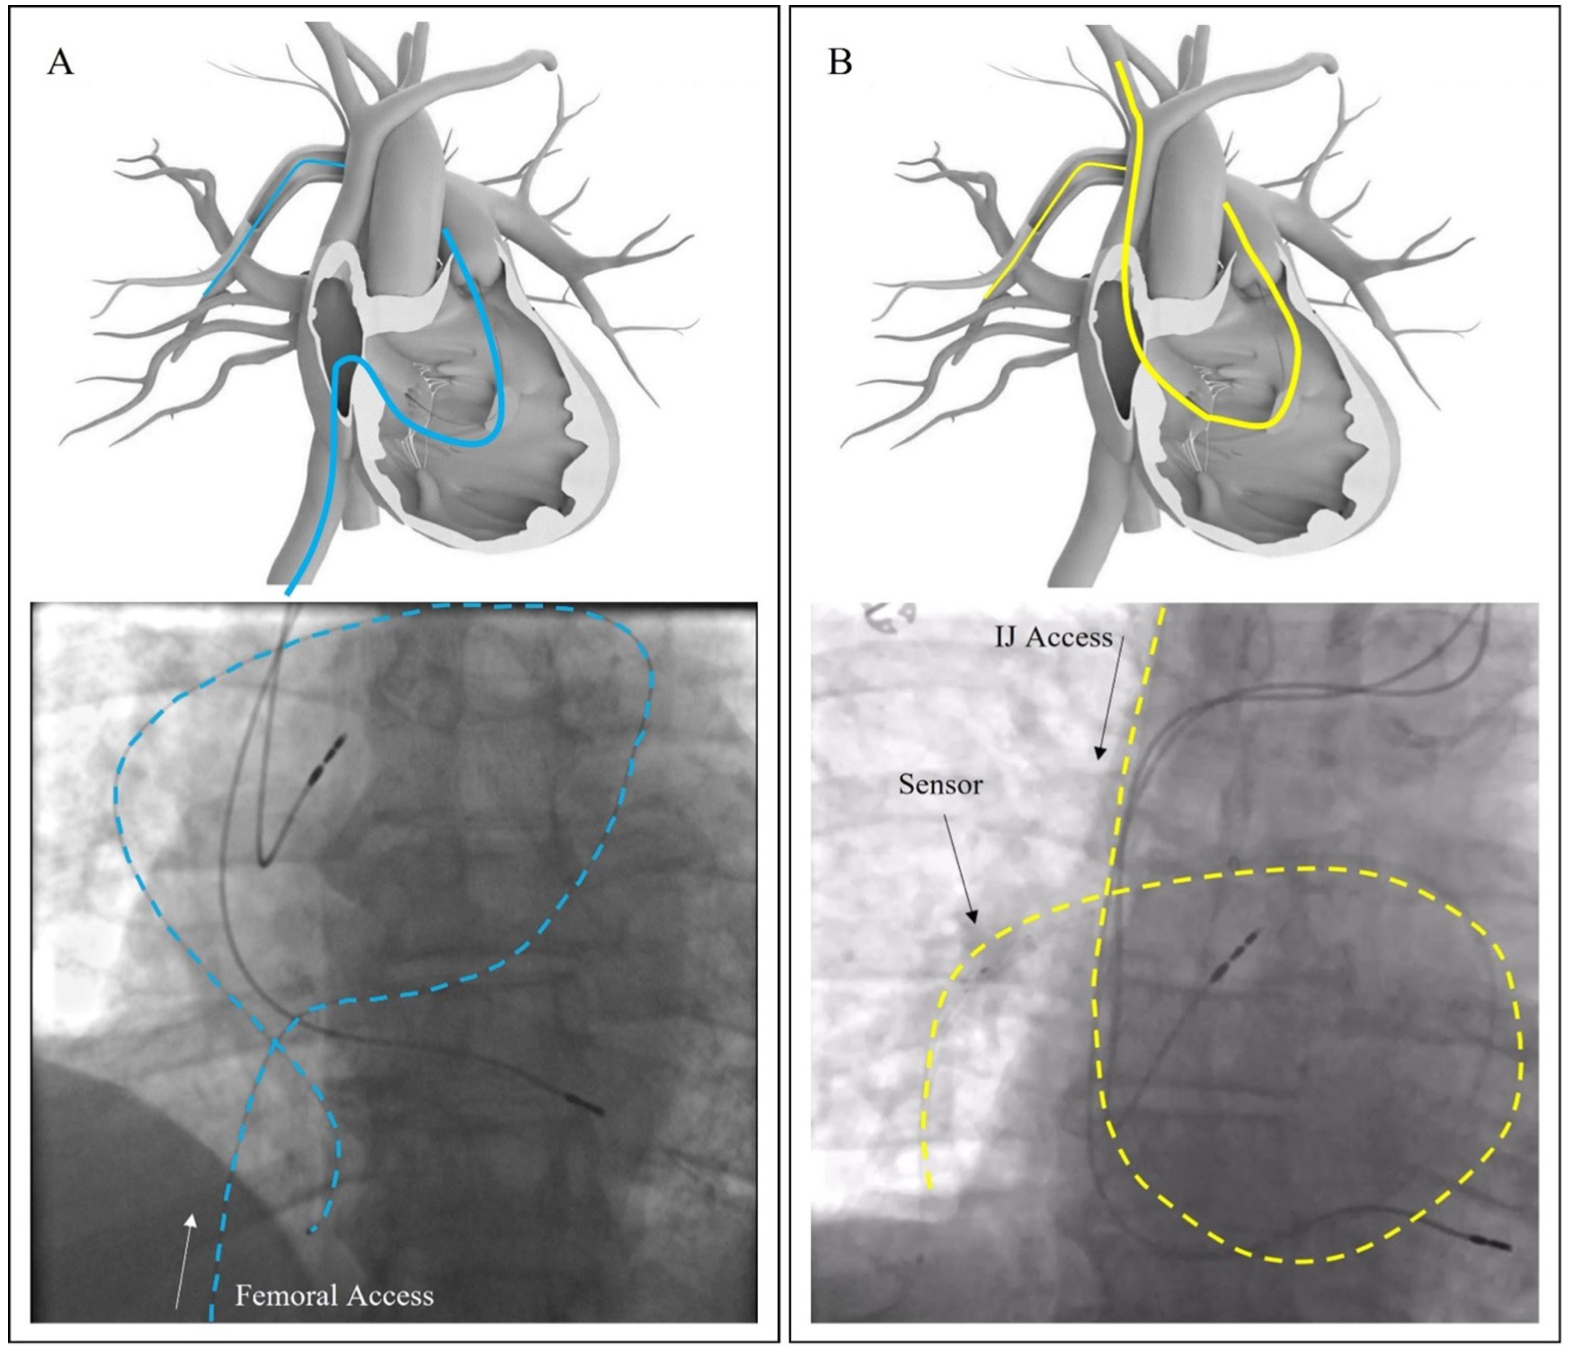

Guide for Implanting the Cordella Pulmonary Artery Pressure Sensor Occluded Pulmonary Artery The selective reverse pulmonary wedge pulmonary vein angiogram can be useful to definitively delineate the anatomy of the. Ct findings of a chronic pe include (i) complete occlusion of a vessel; Measurements of pulmonary artery occlusion pressure (paop) should be performed by slow. When a pulmonary artery is occluded, the pressure in bronchial arteries increases to perfuse pulmonary capillaries. Pulmonary. Occluded Pulmonary Artery.

The Utility of Invasive Hemodynamics in the Management of Cardiogenic Occluded Pulmonary Artery When a pulmonary artery is occluded, the pressure in bronchial arteries increases to perfuse pulmonary capillaries. Measurements of pulmonary artery occlusion pressure (paop) should be performed by slow. Pulmonary vascular disease is the medical term for disease affecting the blood vessels leading to or from the lungs. Ct findings of a chronic pe include (i) complete occlusion of a vessel;. Occluded Pulmonary Artery.